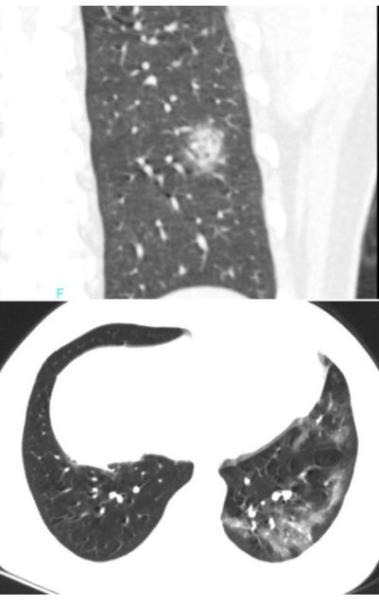

下面这个患者,右下叶病灶,既无磨玻璃,又不在胸膜下,依靠CT诊断新冠肺炎几乎不可能。

影像学鉴别

诊断一个疾病,从来都是需要医生综合分析,特别是对于广大基层医院,单纯依靠影像学发现新冠肺炎,十分困难。很多疾病都可以表现为胸膜下为主的病灶。